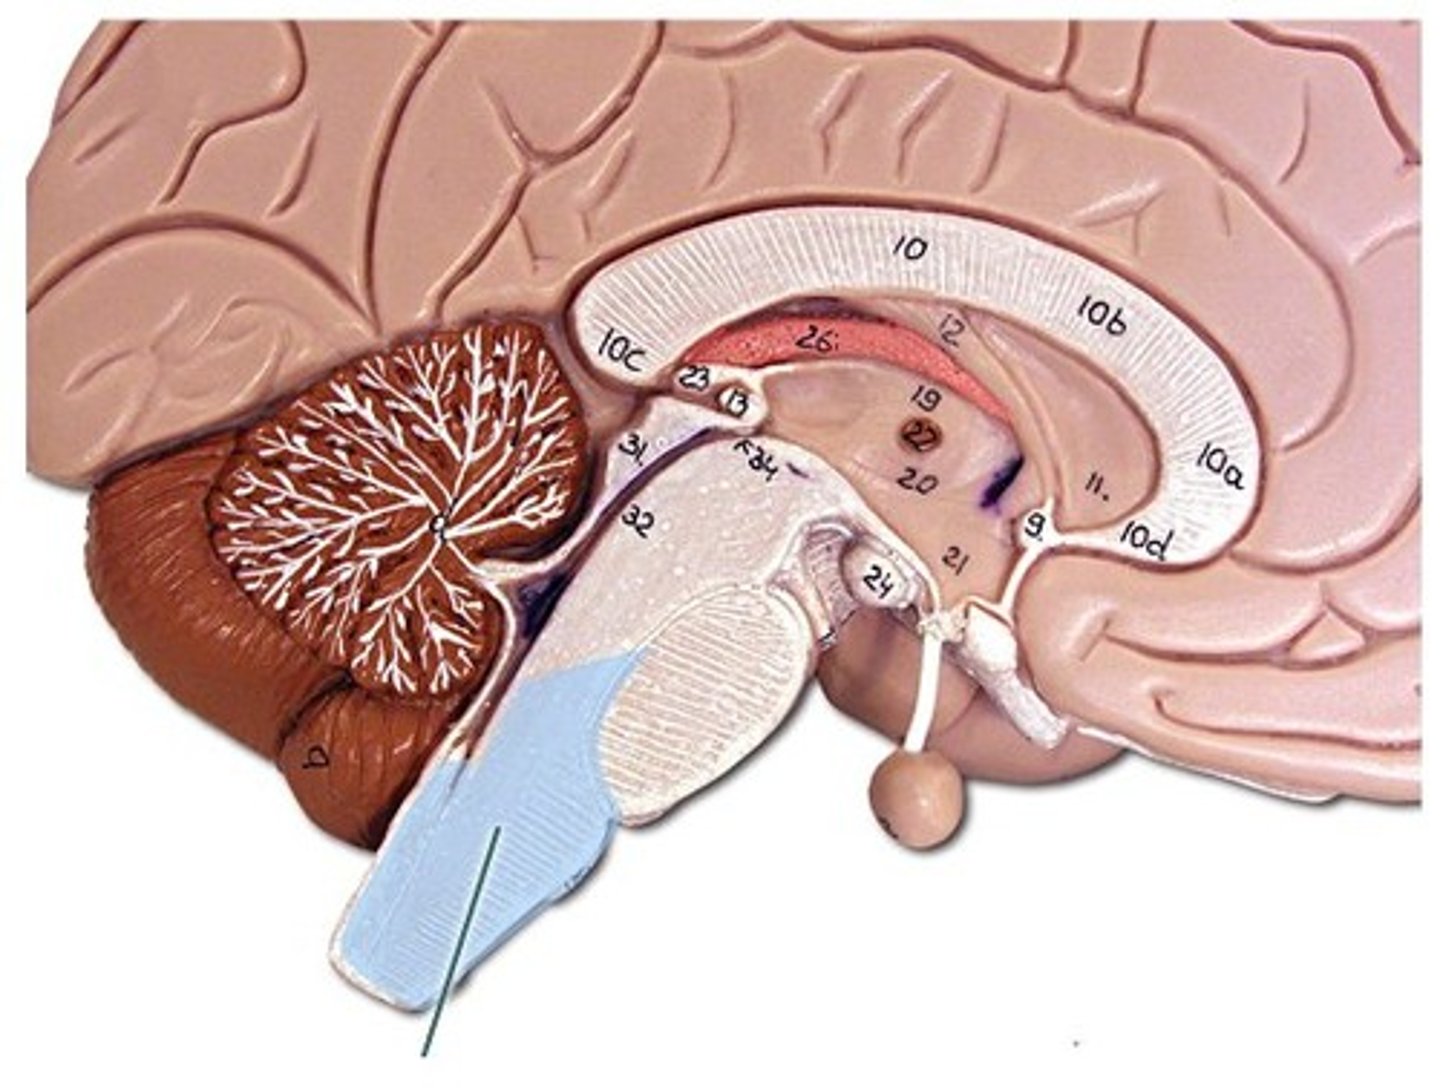

lateral ventricles

third ventricle

fourth ventricle

interventricular foramen

connects lateral ventricles to third ventricle

cerebral aqueduct

connects the third and fourth ventricles

choroid plexus

on the floor of all the ventricles, produces CSF

diencephalon

thalamus and hypothalamus

thalamus

relay station for all somatosensory information

intermediate mass

connection between the two thalami across the third ventricle, dumbbell shape

hypothalamus

brain region (many nuclei) in charge of maintaining homeostasis

pituitary gland

produces hormones

mammillary bodies

olfactory relay stations

epithalamus

region above midbrain that contains pineal gland

pineal gland

regulates sleep-wake cycles, secretes melatonin

cerebellum

balance, equilibrium, gross motor movement

vermis (cerebellum)

The tissue between the two cerebellar hemispheres

arbor vitae

"tree of life," white matter of cerebellum

corpus callosum

the large band of neural fibers connecting the two brain hemispheres and carrying messages between them

septum pellucidum

membrane that separates lateral ventricles

basal nuclei

internal masses of gray matter, smooth out motor movement

fornix

band under septum pellucidum